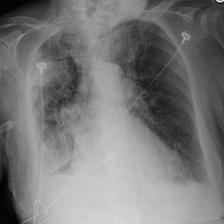

In this regard, VLP in biomedicine and radiology poses a distinctive challenge, as reports routinely include comparisons to prior imaging studies [47, 3, 57]. Without knowledge of this prior image111In the MIMIC-CXR v2 dataset [36], around 40% of reports explicitly reference a previous image. See Appendix B for details., temporal information in the text modality, e.g. “Pneumonia is improving”, could pertain to any image containing “Pneumonia”, producing ambiguity during contrastive training (Figure 1). Despite this, the existing VLP work to date considers alignment between only single images and reports [81, 32, 46, 9], going so far as to remove temporal content from reports in training data to prevent ‘hallucinations’ in downstream report generation[54]. However, temporal information can provide complementary self-supervision, solely by exploiting existing structure, and without requiring any additional data.

In Figure A.3, we show examples of self-attention rollout [1] maps for pleural effusion and consolidation, including radiologist-annotated bounding boxes surrounding the corresponding pathology in each prior and current image.

To model the attention flow through the transformer encoder block, we first average each attention weight matrix across all heads, subsequently we multiply the matrices between every two layers. For every block we add the identity matrix in order to model the residual connections. Last, we only keep the top 10 of attention weights per block to reduce noise in the final rollout map. In contrast to [21], we do not visualize the rollout map with respect to a [CLS] token. Instead, we choose a reference image patch from the center of the radiologist-annotated bounding boxes, marked with in Figure A.3.

We find that the rollout maps in Figure A.3 are in good agreement with radiologist-annotated bounding boxes, i.e., the reference patch attends to other patches within the bounding boxes in the prior and current image. In addition, we find that BioViL-T is robust to pose variations, e.g., in Figure A.3 (a) we show that despite the vertical shift between prior and current image, the reference patch attends to the correct image patches in the prior image.